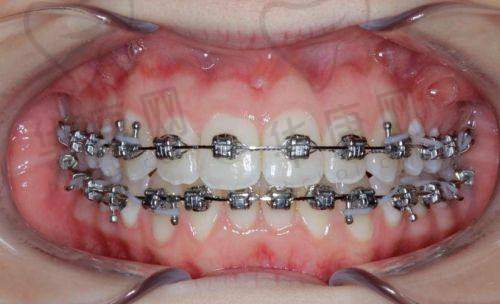

首先,该医院拥有一支经验充足、技术力量雄厚的医师团队。团队中的医生都经过专精的培训和考核,具备扎实的理论基础和丰富的临床经验。他们能够根据每个青少年的牙齿情况和生长发育特点,制定个性化的矫正方案,确保矫正成效达到至佳。例如,医生会通过详细的口腔检查和影像学分析,正确判断牙齿畸形的类型和程度,然后选择合适的矫正方法,如活动矫治器、固定矫治器等。

其次,南宁怡友中海口腔引进了精良的口腔诊疗设备和技术。这些设备和技术能够为青少年早期矫正提供更精细、更效率高的服务。例如,医院采用的数字化口腔扫描技术,可以快速、正确地获取牙齿的三维图像,为医生制定矫正方案提供详细的数据支持。同时,精良的矫正材料也能够提高矫正的舒适度和成效,减少矫正过程中的不适感。